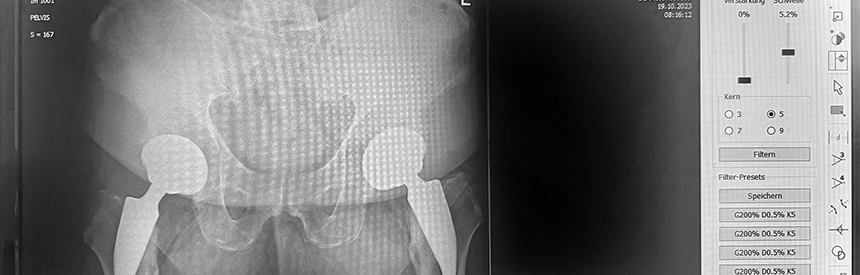

Aufgrund der hohen Dynamik der digitalen Speicherfolie sowie der Sensibilität und Genauigkeit der Ausleseeinheit erhält der Arzt ein Röntgenbild, auf dem sich ein weitaus größeres Spektrum an Informationen befindet, als ihm das aus der konventionellen Radiographie bekannt ist. Durch softwareseitige Unterstützung lassen sich Belichtungsfehler korrigieren, ohne dass eine Neuaufnahme notwendig wird.